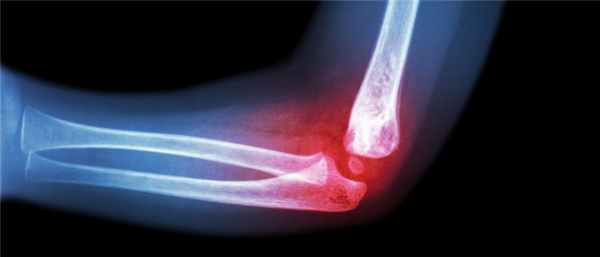

Диагностика вывиха локтевого сустава, как уже сказали, проста. Благодаря доступному визуальному осмотру у опытных не вызывает сомнений постановка диагноза. Однако, для того, чтобы лечение вывиха локтя проходило без скрытых нюансов, делается контрольный рентгенографический снимок. Нередко помимо вывиха имеется и перелом со смещением костных отломков

Вывих локтевого сустава можно определить визуально – предплечье обычно ставится короче, а локоть резко выпирает. Но поскольку могут быть осложнения, которых не видно из-за отека, врачом может быть назначена дополнительная диагностика:

- рентген – он покажет степень поражения сустава, даст понять, повреждены ли мышцы и нервы;

- рентгенография (на основании рентгена сустава определяется степень его поражения, вероятность смещения кости, наличие повреждения мягких тканей, мышц или нервных окончаний)

Диагностика вывиха локтя не представляет сложности для квалифицированного травматолога – узкопрофильного специалиста по патологии локтевого сустава нашей клиники. Пациент, как правило, держит руку в неестественном положении, поддерживая ее здоровой рукой. Травмированный сустав выглядит деформированным, отечным. Крайне болезненной будет попытка совершения каких-либо движений рукой. Для заднего вывиха характерно западение кожи над локтевым отростком, для переднего – отсутствие верхушки локтевого отростка.

Для уточнения положения костей врач проведет деликатную пальпацию травмированного сустава, прощупает состояние мышц и сухожилий. Чтобы исключить возможные переломы костей назначается рентгенография травмированного сустава в двух проекциях.